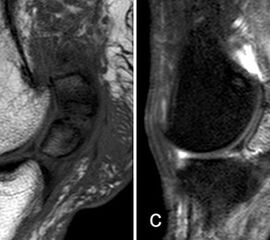

Intermetatarsale Bursitis

Intermetatarsale Bursitis bei rheumatoider Arthritis mit Erguss (a) und deutlicher Synovialitis in mehreren Schleimbeuteln (b).

Abbildung 13

Zwischen den Metatarsaleköpfchen befinden sich kleine Schleimbeutel, die in der Regel MR-tomographisch nicht zu identifizieren sind. Sie werden erkennbar, wenn sie zarte Flüssigkeitsstreifen enthalten, was noch nicht als pathologisch zu werten ist. Eine signifikante Distension und vor allem eine verstärkte Kontrastmittelanreicherung sind Ausdruck einer Bursitis. Die isolierte Bursitis intermetatarsal ist selten und stets hochverdächtig für das Vorliegen einer rheumatischen Grunderkrankung (Abb. 13).

Häufig sind intermetatarsale Bursitiden als Begleitphänomen bei Rupturen oder Degenerationen der plantaren Platte und auch bei Morton-„Neuromen“.